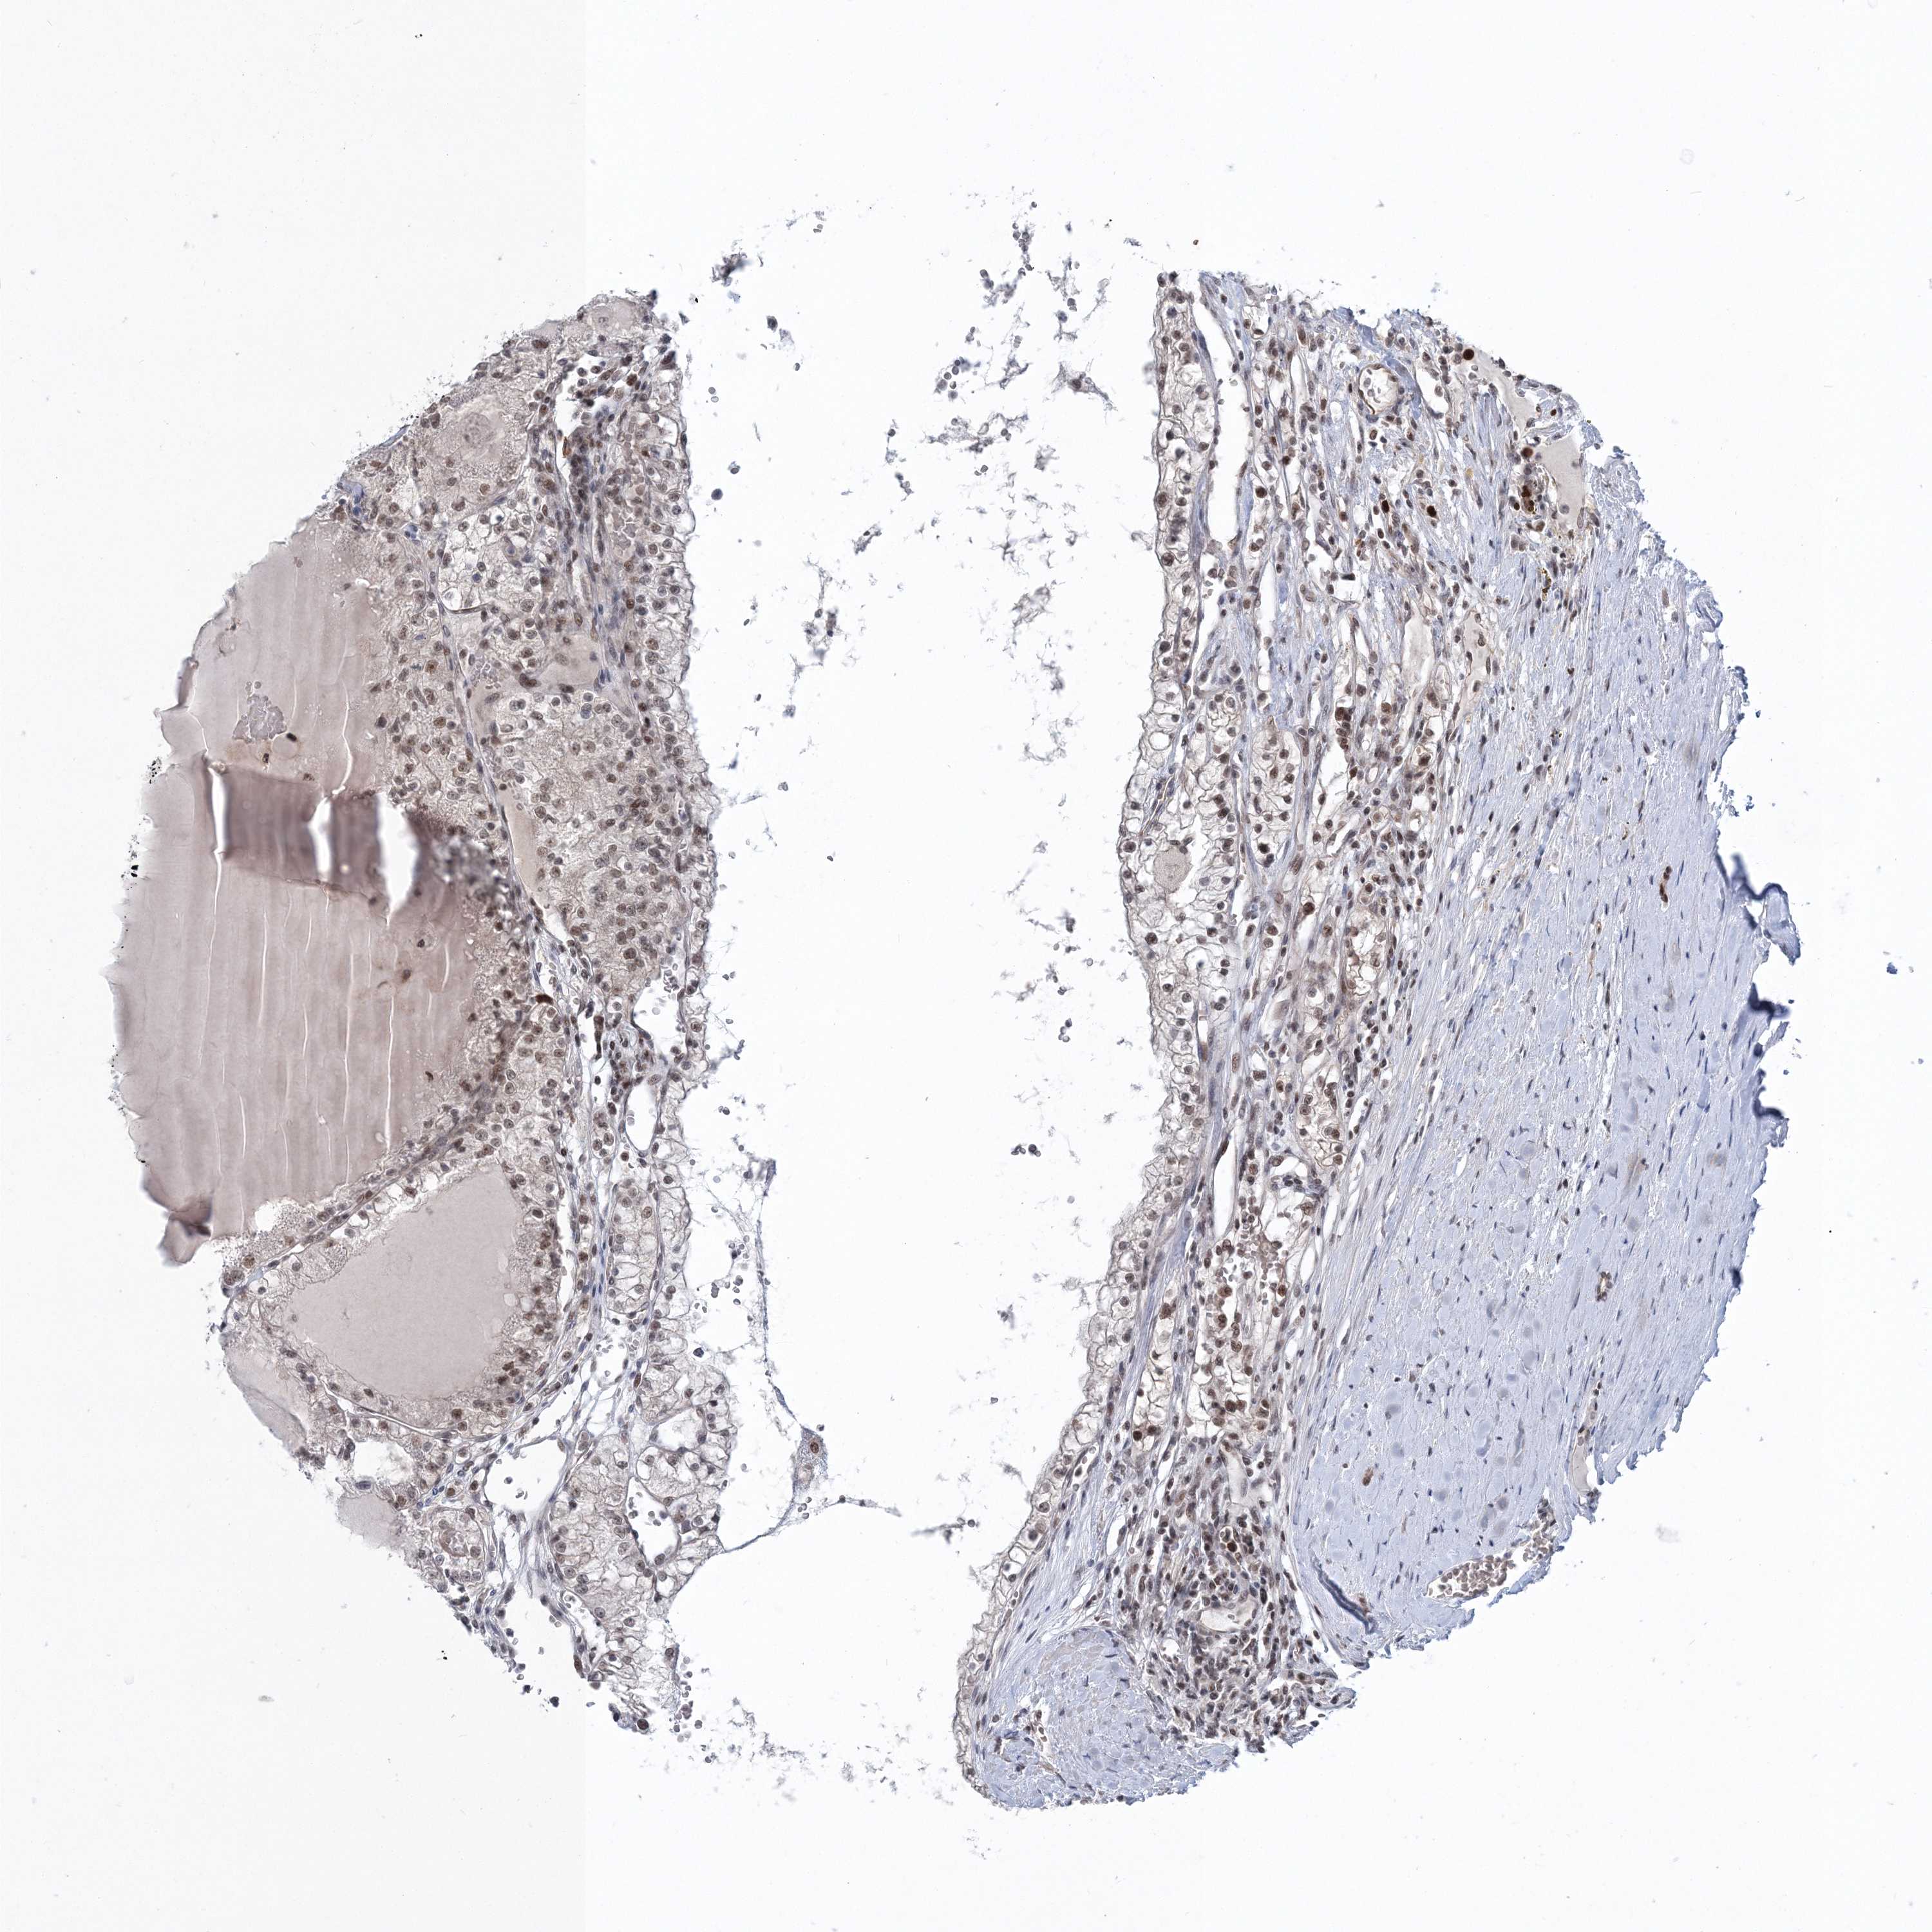

KIDNEY RENAL CLEAR CELL CARCINOMA (VALIDATION) - Interactive survival scatter ploti

The Survival Scatter plot shows the clinical status (i.e. dead or alive) for all individuals in the patient cohort, based on the same data that underlies the corresponding Kaplan-Meier plots. Patients that are alive at last time for follow-up are shown in blue and patients who have died during the study are shown in red.

The x-axis shows the expression levels (FPKM) of the investigated gene in the tumor tissue at the time of diagnosis. The y-axis shows the follow-up time after diagnosis (years). Both axes are complimented with kernel density curves demonstrating the data density over the axes. The top density plot shows the expression levels (FPKM) distribution among dead (red) and alive patients (blue). The right density plot shows the data density of the survived years of dead patients with high and low expression levels respectively, stratified using the cutoff indicated by the vertical dashed line through the Survival Scatter plot. This cutoff is automatically defined based on the FPKM cutoff that minimizes the p-score. The cutoff can be changed by dragging the vertical line or by entering a cutoff value in the square labeled "Current cut-off".

Under the Survival Scatter plot the p-score landscape (black curve; left axis) is shown together with dead median separation (red curve; right axis). Dead median separation is the difference in median mRNA expression between patients who have died with high and low expression, respectively. It is calculated as follows: median FPKM expression of dead patients with high expression - median FPKM expression of dead patients with low expression. This is intended to aid the user in visually exploring custom cutoffs and the associated p-scores and dead median separation.

Individual patient data is displayed and can be filtered by clicking on one or more of the category buttons on the top of the page. Categories describing expression level and patient information include: high, low, alive, dead, female, male and tumor stages. The scale of the x-axis can be toggled between linear and log-scale by clicking on the "x log" button. Mouse-over function shows TCGA ID, patient information and mRNA expression (FPKM) for each patient.

& Survival analysisi

Kaplan-Meier plots summarize results from analysis of correlation between mRNA expression level and patient survival. Patients were divided based on level of expression into one of the two groups "low" (under cut off) or "high" (over cut off). X-axis shows time for survival (years) and y-axis shows the probability of survival, where 1.0 corresponds to 100 percent.

PDS5A is not prognostic in Kidney Renal Clear Cell Carcinoma (validation)

Best expression cut offi

Based on the FPKM value of each gene, patients were classified into two groups and association between prognosis (survival) and gene expression (FPKM) was examined. The best expression cut-off refers the FPKM value that yields maximal difference with regard to survival between the two groups at the lowest log-rank P-value. Best expression cut-off was selected based on survival analysis .

When clicking on this number, the vertical dashed line indicating cut-off, the interactive survival plot, and the Kaplan-Meier curve will be adjusted to show results based on the best expression cut-off.

: 32.5

TCGA RNA samplesi

RNA-seq data is reported as average FPKM (number Fragments Per Kilobase of exon per Million reads), generated by the The Cancer Genome Atlas (TCGA) .

Normal distribution across the dataset is visualized with box plots, shown as median and 25th and 75th percentiles. Points are displayed as outliers if they are above or below 1.5 times the interquartile range. FPKM values of the individual samples are presented next to the box plot.

Average pTPM 32.2

Number of samples 100